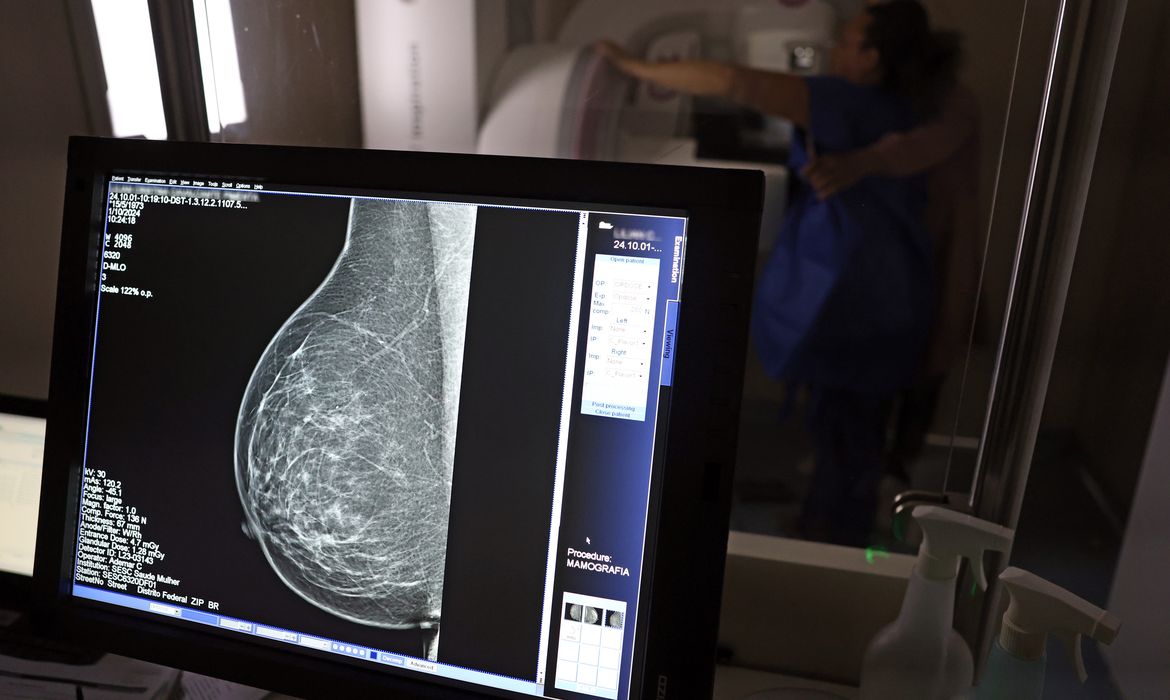

Falta de acesso a mamógrafos limita prevenção do câncer de mama

No mês de conscientização sobre o câncer de mama, um relatório destaca a importância de acesso igualitário ao rastreamento e tratamento da doença. Segundo o Atlas da Radiologia no Brasil, do Colégio Brasileiro de Radiologia e Diagnóstico por Imagem (CBR), o acesso aos mamógrafos ainda é um desafio.

O país tem 6.826 equipamentos registrados, sendo 96% em funcionamento. Metade deles está disponível no Sistema Único de Saúde (SUS), responsável por atender 75% da população. Isso equivale a 2,13 mamógrafos por 100 mil habitantes dependentes do SUS.

Na saúde suplementar, que cobre 25% da população, o cenário é mais favorável: 6,54 aparelhos por 100 mil beneficiárias, quase o triplo da rede pública. O Acre exemplifica essa disparidade — são 35,38 mamógrafos por 100 mil habitantes na rede privada, contra 0,84 no SUS.

O Brasil tem uma cobertura muito baixa de mamografias: 24%. O ideal recomendado pela Organização Mundial da Saúde é de 70%. Mesmo em lugares como o estado de São Paulo, que tem a maior concentração de mamógrafos do país, a taxa gira em torno de 26%.

Em setembro, o Ministério da Saúde ampliou as diretrizes de rastreamento, recomendando que mulheres entre 40 e 49 anos realizem mamografias, mesmo sem sintomas. De acordo com o Instituto Nacional do Câncer (Imca), mais de 73 mil mulheres recebem o diagnóstico de câncer de mama anualmente no Brasil.

“O que é efetivo na redução da mortalidade é você descobrir o tumor antes de ter sintoma clínico. Quanto menor o tumor, melhor para a gente descobrir o tratamento e maior a chance de cura. E a gente só consegue fazer isso com exames de imagem”, diz Ivie.

Ela explica que no caso de diagnóstico de um câncer de mama com menos de 1 cm, a chance de cura é de 95% em cinco anos, independentemente se ele é do tipo mais agressivo. “E esses tumores só vão ser detectados na mamografia. Essas pessoas que têm que ir fazer mamografia são mulheres saudáveis. Não são mulheres doentes”, acrescenta.